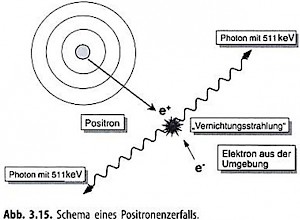

PET unterscheidet sich von den konventionellen Untersuchungstechniken im Wesentlichen durch die Art der verwendeten Radionuklide. Beim PET werden Radionuklide verwendet, die bei ihrem Zerfall Positronen aussenden (= emittieren).

Vorgang des ß+-Zerfall

Positronenstrahler haben einen Überschuss an Positronen und sind deshalb instabil. Um in einen stabilen Zustand zu kommen, wird vom Atomkern Positronen emittiert. Diesen Vorgang nennt man auch ß+-Zerfall. Die emittierten Positronen treffen auf Elektronen in der Umgebung. Das Zusammentreffen eines Positrons mit einem Elektron führt zu einer Vernichtungsreaktion. In dieser wandeln sich die beiden Teilchen zu Gammastrahlung, der sogenannten Vernichtungsstrahlung um. Die Vernichtungsstrahlung hat jeweils eine Energie von 511 keV und breitet sich auf einer Linie in entgegengesetzter Richtung in einem Winkel von 180 ͦ aus, und zwar genau zeitgleich.

Datenregistrierung PET:

Nur diese zeitgleichen, genau gegenüber liegende Ereignisse werden von einer PET-Kamera mit Hilfe eines Detektorringes registriert.  Der Computer erkennt, dass zwei Ereignisse zusammengehören, wenn sie nahezu zeitgleich gemessen werden.

Der Computer erkennt, dass zwei Ereignisse zusammengehören, wenn sie nahezu zeitgleich gemessen werden.

Solche zwei Werte bezeichnet man als koinzident (zeitgleich). Die Lokalisation erfolgt durch gegenüberliegende in Koinzidenz geschaltete Detektoren.

Die gleichzeitige Detektion der beiden Energieteilchen erlaubt es, die Linie, auf der der Zerfall stattgefunden hat, zu bestimmen. Aus der Überlagerung sehr vieler dieser Linien wird durch Rekonstruktionen die Radionuklidverteilung des Patienten bildlich dargestellt.

Diese paarweise Detektion der Energieteilchen führt zu einer gegenüber anderen nuklearmedizinischen Verfahren etwa 100fach höheren Empfindlichkeit und zu einer erhöhten Ortsauflösung.